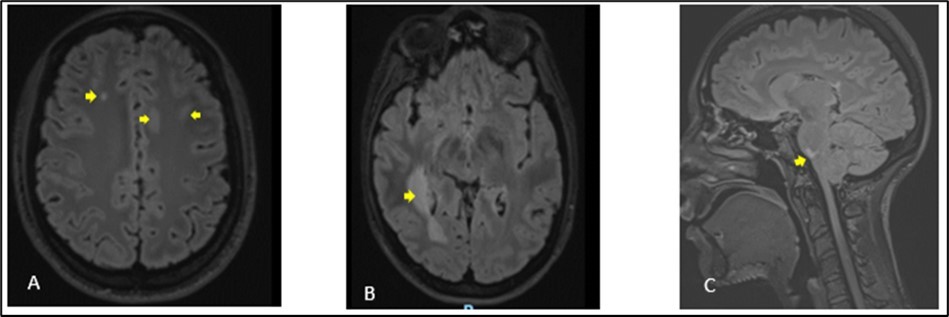

A 27-year-old girl presented at the emergency department, at a hospital in the Paris region on March 9, 2020 with complaints of left interscapular pain, paresthesias and weakness in the ipsilateral upper limb. These symptoms followed paresthesias on the fingertips of her right hand the day before her admission. She did not report fever, sphincter disorder or gait disturbance. No eye symptoms reported. In her medical history, she was treated two weeks earlier for pneumonia with COVID-19. There was no another previous infectious episode apart from the COVID-19. She had no history of diabetes, hypertension, cerebrovascular disease or migraine. She had not history of multiple sclerosis or Neuromyelitis Optica Spectrum Disorder (NMOSD). There was no history of smoking, contraception drugs intake or any prolonged drug intake. On the first examination in the neurology department where she was transferred on the same day of her admission, she had good general condition and was apyretic. She had a pulse rate of 74/min and the blood pressure was at 130/80 mmHg. The neurological evaluation showed on the left side, a muscular weakness grade 4 in the proximal part and grade 3 in the distal part of upper limb, and in the lower limb, the weakness graded at 3 in the distal part, using the Medical Research Council Scale (MRC) for muscle strength. There was no weakness on the right side. Deep tendon reflexes in both left and right were normal. Babinski sign was found on the left side. She presented tactil and algic hypoesthesia in the lower left limb ascending until the C4 level in the left side. There was no perineal sensitive trouble. The remain neurological exam including, higher functions, cranial nerves, was with no particularity. Otherwise, cardiovascular and respiratory systems examination were within normal limits. Blood laboratory tests were within the normal ranges, including complete blood count (CBC), C-Reactive protein, renal and liver functions and blood serum ionogram. Human Immunodeficiency Virus (HIV) tests including p24 antigen and antibodies to HIV were negative. Syphilis serology and Aquaporin 4 antibody were also negative. Encephalic Magnetic Resonance Imaging (MRI) demonstrated scattered hyperintense lesions on FLAIR imaging in deep hemispheric and juxtacortical white matter in supratentorial and in infratentorial floors (Figure 1). Medullary MRI showed T2 hyperintense lesions in left cervical hemi-marrow extending from C3 to C6, at T3, T4, T11 and T12 levels (Figure 2). These lesions were not enhanced after injection of gadolinium. The Cerebrospinal fluid (CSF) appeared to be colorless and clear with no cell detected microscopically; cerebrospinal protein level, 0.4 mg/L, glucose (Glu) level, 3.2 mmol/L; and instant blood glucose level, 5.2 mmol/L. CSF bacterial culture demonstrated no growth after 3 days, and herpes simplex virus 1 and 2, varicella-zoster virus test was negative. Reverse transcription-polymerase chain reaction (RT-PCR) assay test for COVID-19 was negative in the CSF. The final diagnosis was an ADEM secondary to novel coronavirus (nCov) infection. She was given methylprednisolone (1000 mg IV per day for 5 days) followed by Intravenous Immunoglobulin (IVIG) therapy at 0.4 g/kg daily for 5 days. Together with chemotherapy, she received physiotherapy coupled with occupational therapy. The outcome was good with improvement of weakness and paresthesias. There was residual tingling on the fingertips of the left hand. The patient was discharge on day 13.

Figure 1.Cerebral MRI in FLAIR sequences showing multiple hyperintense lesions at the supratentorial (A, B) and infratentorial (C) levels. The largest supratentorial lesion (B) is opposite the right paraventricular white matter, at the level of the posterior horn and measures 55 x 17 mm axially. Presence of a lesion of pons (C) of 6.5 mm.

We have described a case of ADEM post COVID-19 infection in a 27-year-old girl who was taken care of in a hospital in the Paris region. She was treated in the same hospital 2 weeks earlier for an acute respiratory distress syndrome caused by COVID-19 infection. The period of the study was at the beginning of the outbreak of COVID-19 infection in France. COVID-19 is a new entity caused by the severe acute respiratory syndrome coronavirus 2 (SARS CoV-2). It is known to cause respiratory complications, from mild upper respiratory symptoms to acute respiratory failure. ADEM is an immune-mediated inflammatory disorder of the CNS characterized by a widespread demyelination that predominantly involves the white matter of the brain and spinal cord. The condition is usually precipitated by a viral infection or vaccination 7. For this, it is also named post-infectious encephalomyelitis. The infection typically comes before the onset of symptoms of approximately 2 days to 4 weeks 8. This was the case of our patient who presented two weeks before the onset of neurological symptoms, a pulmonary infectious episode for which the etiological research revealed a COVID-19 infection. The pathological abnormalities during ADEM are post-infectious changes of immune origin affecting the central nervous system. These changes are present in the small blood vessels of both white and grey matters. As the lesions become older, the macrophages increase and lymphocytes decrease in number. At a late stage of disease foci of fibrillary fibrosis can also be seen in adjacent brain tissue. Although postinfectious encephalomyelitis typically involves the white matter, lesions in grey matter have also been seen and may involve basal ganglia and the thalamus 3, 4. Due to the impossibility to perform an anatomopathological examination in our patient, MRI of the CNS constitute a reliable tool to translate the diffuse CNS damages of the brain as well as of the marrow. These elements are well presented on the imaging performed by our patient (Figures 1, 2). There is a lack of detection in CSF in most cases besides evident inflammation. This raises the possibility that the majority of ADEMs associated with COVID-19 could be the result of immune-mediated mechanisms or molecular mimicry which generates an aberrant neuro-inflammatory loop, so the virus does not need to cross the blood-brain barrier to cause damage to the CNS 9. As with ADEM occurring after other viral infections, the mechanism would be the same in the case of COVID-19 infection. The presence or history of any other systemic infection, particularly viral, would have made the diagnosis unlikely. As the patient had no other infection apart from COVID-19 in the days preceding the neurological symptoms, it is therefore perfectly legitimate to consider this infectious episode as the trigger for the cascade of immune reactions at the origin of the neurological symptoms. In most cases, ADEM has a monophasic course and is self-limiting, with return to neurological baseline within 3 months after the onset of symptoms. Occasionally, a subset of ADEM patients with relapsing disorders, including recurrent disseminated encephalomyelitis (RDEM), multiphasic disseminated encephalomyelitis (MDEM), neuromyelitis optica spectrum disorders (NMOSD), and multiple sclerosis have been reported 10. The clinical presentation is heterogeneous. Typically, patients show prodromal symptoms such as fever, headache, malaise, nausea, and vomiting. The acute phase occurs with encephalopathy, characterized by altered behavior including irritability, confusion and consciousness like lethargy, stupor, or coma associated with multifocal or focal neurological deficits depending on the area involved in the demyelinating process 11. Other neurological findings have been reported in ADEM related to COVID 19. Laura Zelada-Ríos reported in 2021 pyramidal signs (44.4%), brainstem signs (11.1%), cerebellar signs (22.2%), seizures (33.3%) and peripheral nerve compromise (11.1%) 12. ADEM in COVID 19 pediatric patients have been also reported in children 6, 13. MRI plays a key role in the diagnosis of ADEM and should be performed as soon as it is suspected. The typical findings are identified as lesions with signal hyper-intensity in FLAIR and T2 sequences, they are usually multiple, asymmetric, irregular, poorly defined, and greater than 2 cm. In general, the white matter is affected, although it may involve the deep gray matter, the brainstem, the cerebellum, and the spinal cord 12. MRI is also used to consider differential diagnoses 14 multiple sclerosis (MS), neuromyelitis optica (NMO), and neuromyelitis optica spectrum disorder (NMOSD), which can overlap with ADEM in presentation 15. Among these previous diagnoses, multiple sclerosis remains the most important differential diagnosis of ADEM. Both clinically and paraclinically, these 2 pathologies share almost the same criteria. Thus, Swharz et al, in a cohort of 40 patients, fail to identify any exclusive feature characteristic of either condition. Similarly, cerebrospinal fluid findings are not distinctive enough to allow differentiation between ADEM and multiple sclerosis in a single patient. Even MRI studies were not able to differentiate ADEM from multiple sclerosis. Approximately, 50% of the patients with ADEM had MRI features that were suggestive of multiple sclerosis. however, fever, loss of consciousness, and meningism are infrequently observed but are highly suggestive of ADEM because these symptoms are rare in multiple sclerosis 16. It results from this study of Swharz, that the chronology of the neurological symptoms with a pre-existing systemic infection, viral especially constitutes a very determining profile. These data of the interrogation were at the base of the diagnosis of ADEM post covid of our patient more especially since there were no clinical or paraclinical arguments in favor of another potential differential diagnosis, that is Devic's neuromyelitis optica. Differences exist between encephalitis associated with COVID-19 and ADEM associated with COVID-19, one of them is temporality. Unlike ADEM, neurological symptoms usually appear simultaneously with respiratory symptoms in COVID-19-associated encephalitis. Brain inflammation expressed by pleocytosis is more frequent in encephalitis associated with COVID-19 17. Sharing the same pathophysiological mechanisms as other post-infectious encephalomyelitis, the principles of the treatment of post-COVID ADEM therefore remain similar. The treatment of ADEM is targeted to suppress a presumed aberrant immune response to an infectious agent or a vaccination. Treatment with intravenous corticosteroids (methylprednisolone) or adrenocorticotrophic hormone in large doses has been shown to improve the outcome 18, 19. Corticosteroids are usually associated with plasmapheresis and intravenous immunoglobulin. This association have been shown to produce dramatic improvement in some cases where corticosteroids have failed 16. In some cases, cytotoxic agents have been used with success 18. Functional rehabilitation as a support treatment is a useful contribution even if the publications do not usually mention it. Regarding clinical outcomes, it is generally favorable in the cases of ADEM. This was the case of our patient as well as the results reported by L. Zelada-Ríos et al. 12.